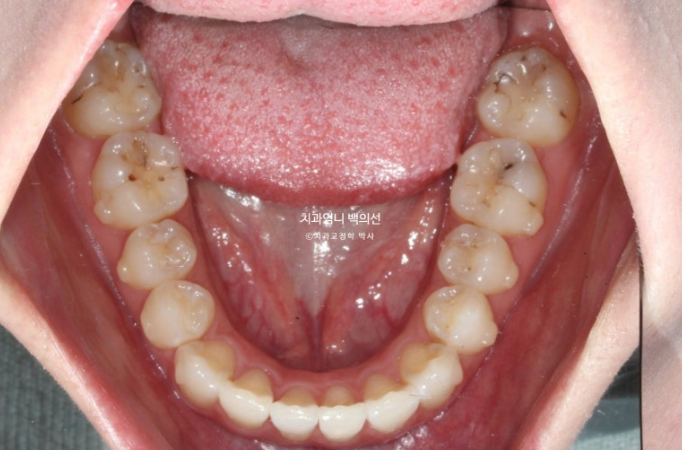

위 아래 치아중심선이 어긋나 있고 아래 앞니 하나가 솟으면서 뒤로 들어가 있습니다.

어금니 교합은 좋죠.

이런 경우는 인비절라인의 프로그램 중 인비절라인 라이트로 교정하면 기간 비용대비 환자분의 만족도가 가장 좋습니다.